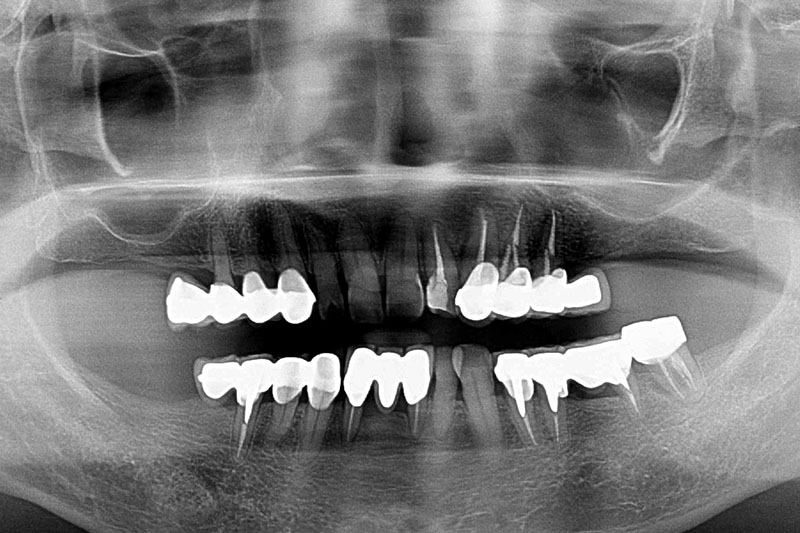

缺牙多顆-全口X光攝影

案例一

術前

術後